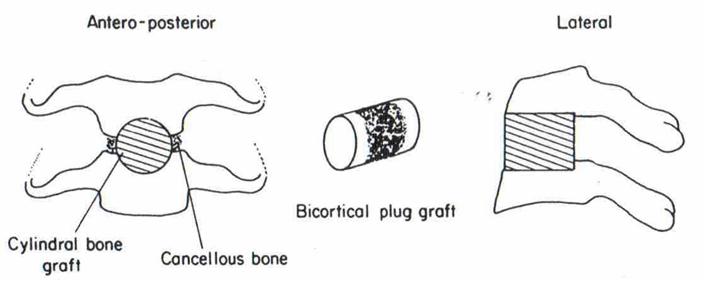

В шейном отделе позвоночника выполняется преимущественно удаление грыж межпозвоночных дисков по Кловарду с последующей стабилизацией костным аутотрансплантатом и фиксацией пластинкою Medtronic или устанавливается кейдж фирмы Stryker.

Далее после образования трепанационного окна проводится дополнительный рентгенологический контроль пораженного уровня. Затем смещаются полая вена и аорта, перевязываются сегментарные сосуды, постепенно удаляется диск, задняя продольная связка, сама грыжа, при необходимости – остеофиты. Обследуется эпидуральное пространство, исключается наличие секвестров. В заключении устанавливается стабилизирующая система (межтеловой корпородез 1 или 2 кейджами длиной примерно 20 мм и диаметром от 12 до 14 мм).